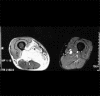

Diabetic myonecrosis is an underreported complication of long-standing, poorly controlled diabetes mellitus which is usually self-limiting and responds well to conservative management. Patients frequently have microvascular complications, and although short-term prognosis is good, the long-term prognosis is poor. We report four cases of diabetic myonecrosis admitted in a tertiary care hospital.